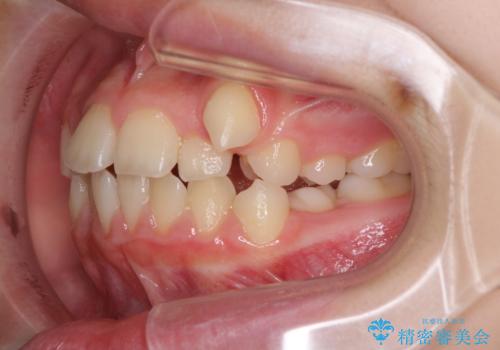

- 八重歯と乳歯が残っていることを気にして来院された患者様です。

乳歯が3歯残っており、下顎は左右ともに後続永久歯がない状態でした。

口元が突出しており、口が閉じにくかったため、乳歯を含め上下5歯を抜歯して矯正治療を行うこととしました。

下顎の乳歯は永久歯と比べて幅が大きいため、抜歯した場合のスペースが大きく、治療には長期間を要することが一般的です。

今回の患者様は中学生ということもあり、成人の患者様と比べ動きが速く、2年間で治療を終えることができました。